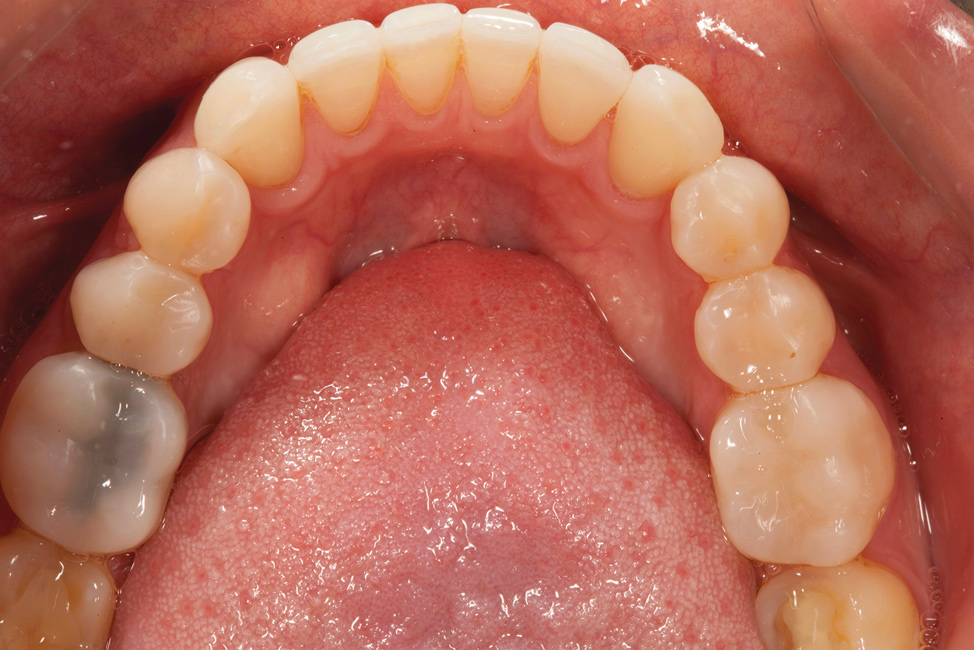

Fig 4. Preoperative occlusal view of upper arch.

Figure 4

A comprehensive examination was carried out, and preoperative photographs were taken (Figure 1 through Figure 4). The patient presented with fair oral hygiene and slight, generalized tissue inflammation. Caries and defective restorations were detected on teeth Nos. 4, 5, 13, and 14. The crown on tooth No. 12 was showing signs of leakage, and although the endodontic access cavity had been temporarily restored with composite, this endodontic re-treatment was acceptable and the tooth was otherwise symptom-free. Erosion was present on most of the posterior teeth and the cuspids, and abrasion was noted on teeth Nos. 4, 5, 10, 11, 20, 21, 22, 28, and 29. An examination of the patient's muscles, joints, and bite revealed no joint sounds, a normal range of motion, and negative joint load and immobilization tests.

The dentofacial examination revealed a low smile line with no incisor display when the lips were in repose. The anterior teeth were chipped and worn, and their overall color was darkened. The buccal corridors were deficient, and the failing crown on tooth No. 12 was visible in a full smile.